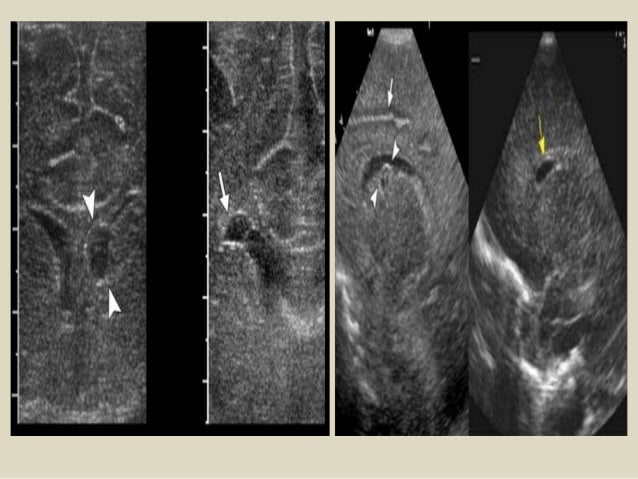

31. 31. Porencephalic cyst: Large foci of intraventricular/intraparenchymal bleed could lead to a cavitating destructive lesion in the brain parenchyma. After resolution and evacuation of the hematoma, the cavity of the lesion communicates with the ventricular system, leading to the formation of a porencephalic cyst. Porencephalic cysts, which are, often, a sequel of grade 4 hemorrhages are usually associated with higher neurodevelopmental defects . Coronal USG and the high-resolution parasagittal view demonstrating a large porencephalic cyst communicating with the left lateral ventricular cavity.